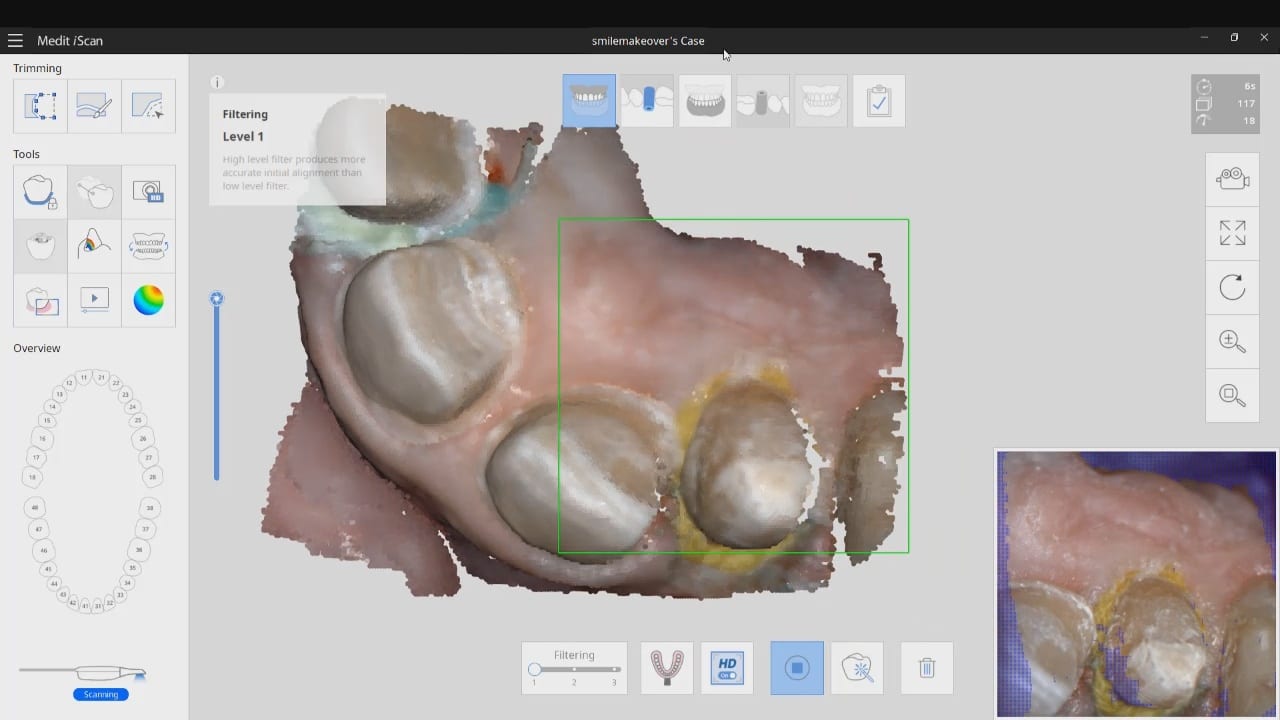

Post op intra-oral scan with Medit i500 to capture irritated and hemorrhaging tissue (for demonstration purposes only)